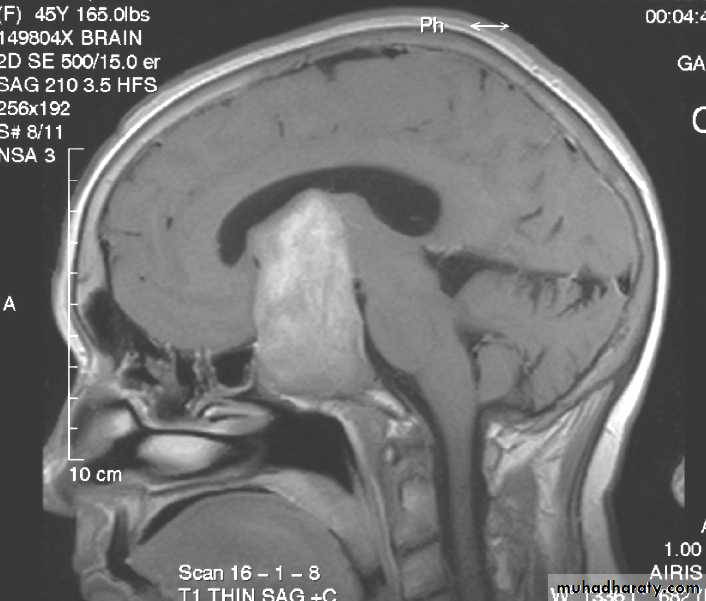

PITIUTARY ADENOMA SAGGITAL MRI

PINEAL TUMOR SAGGITAL MRI